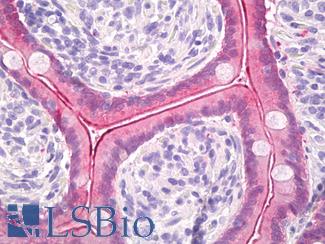

Anti-Smooth Muscle Actin antibody IHC of human prostate, smooth muscle. Immunohistochemistry of formalin-fixed, paraffin-embedded tissue after heat-induced antigen retrieval. Antibody LS-B7351 dilution 1:50.

SMMHC

Anti-Myosin, Smooth Muscle Heavy Chain antibody IHC of human prostate. Immunohistochemistry of formalin-fixed, paraffin-embedded tissue after heat-induced antigen retrieval. Antibody LS-B5148 concentration 20 ug/ml.